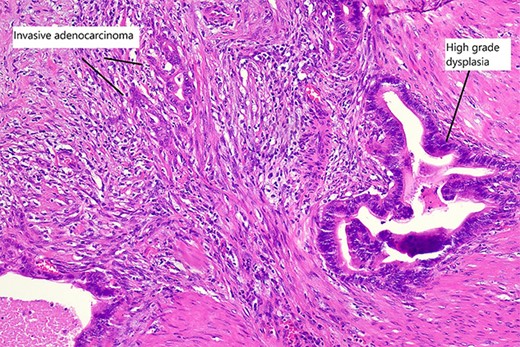

Final histopathological assessment of the resected specimen reported a common bile duct adenocarcinoma (cholangiocarcinoma) measuring 37Â mm in greatest dimension with extensive perineural, periductal, perinodal and peripancreatic soft tissue involvement. Metastatic carcinoma was found in 3/17 lymph nodes resected. The cholangiocarcinoma was staged as pT2N1M0. The gallbladder was found to have extensive high-grade biliary intraepithelial neoplasia with a primary gallbladder adenocarcinoma measuring 18Â mm in greatest dimension entirely separate from the cholangiocarcinoma (Fig. 5). The patient recovered well from the procedure and was discharged home from hospital on post-operative Day 15. She has proceeded to have further treatment with adjuvant chemotherapy.

High magnification slide showing high-grade dysplasia and invasive adenocarcinoma of the gallbladder after haematoxylin and eosin staining.